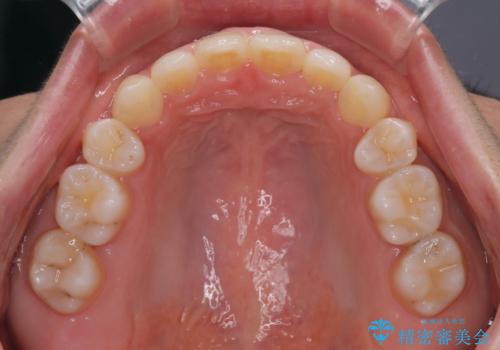

口ゴボが気になる 上下4本の抜歯矯正

- 前歯のデコボコやクロスバイト、口元の突出感を気にして来院された患者様です。

上下左右の第一小臼歯4本を抜歯して、ワイヤー装置にて矯正治療を行うこととしました。

途中出産や育児があり、治療期間長くなってしまいましたが、ストレスなく唇が閉じられるような口元に仕上げることができました。